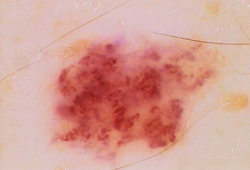

Оптический дерматоскоп "Люминис" обладает наиболее высокими характеристиками для использования в дерматологических отделениях и кабинетах ЛПУ и в частной практике, осуществляющих приём и лечение пациентов с новообразованиями и другими патологиями кожи и волос, включая следующие:

Дерматология:

● невус сложный, невус дермоэпидермальный, Compound Melanocytic Nevus ● невус интрадермальный,

Intradermal Nevus ● пограничный пигментный невус, Borderline Melanocytic Tumor ● невус Шпиц (Спитц),

Spitz Nevus ● юношеская меланома, Juvenile Melanoma ● веретёноклеточный невус, Spindle Cell Nevus

● эпителиоидный невус, Epithelioid Nevus ● невус из баллонообразующих клеток, Balloon Cell Nevus

● невус Саттона, Sutton Nevus ● галоневус, Halo-nevus ● синий невус,

голубой невус, Blue Nevus ● невус Ядассона-Тьеша, Jadassohn-Tièche Nevus ● невусы меланоцитарные

врождённые, родимое пятно, Congenital Melanocytic Nevus ● телеангиоэктазия, Telangiectasia ● ретикулярный

варикоз, Reticular Varicose ● базалиома, Basalioma ● пигментированная базалиома, Melanocytic Basalioma

● невус диспластический, Dysplastic Nevus ● лентиго, Lentigo ●

злокачественное лентиго, Malignant Lentigo ● лентигинозный невус, Lentiginous Nevus ● лентиго-меланома,

Lentigo Malignant Melanoma ● меланома, Melanoma ● меланома in situ, Melanoma in situ

● узловая меланома, нодулярная меланома, Nodular Melanoma ● лентигинозная меланома, Lentiginous Melanoma

● акральная меланома, Acral Melanoma ● десмопластическая меланома, Desmoplastic Melanoma

● Baloon Cell Melanoma, Меланома баллонных клеток.